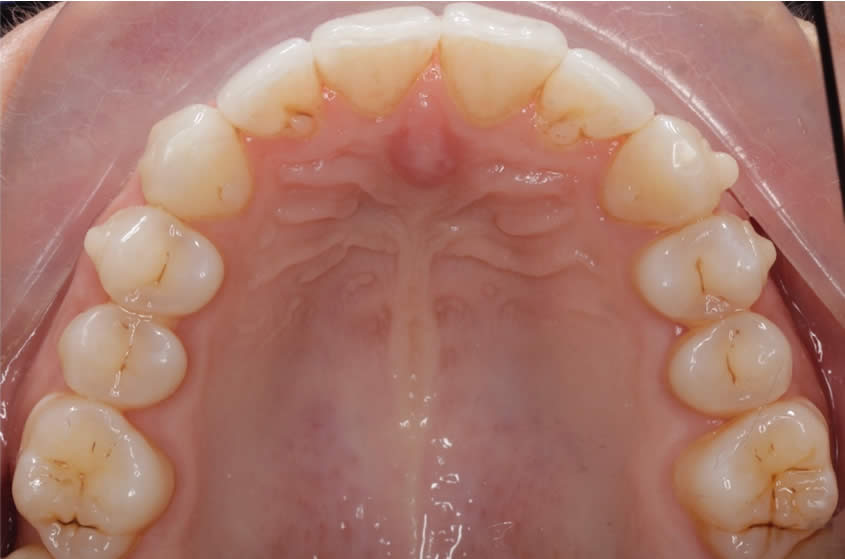

Patient Teeth Straightening Case

Teeth Straightening - Case 2